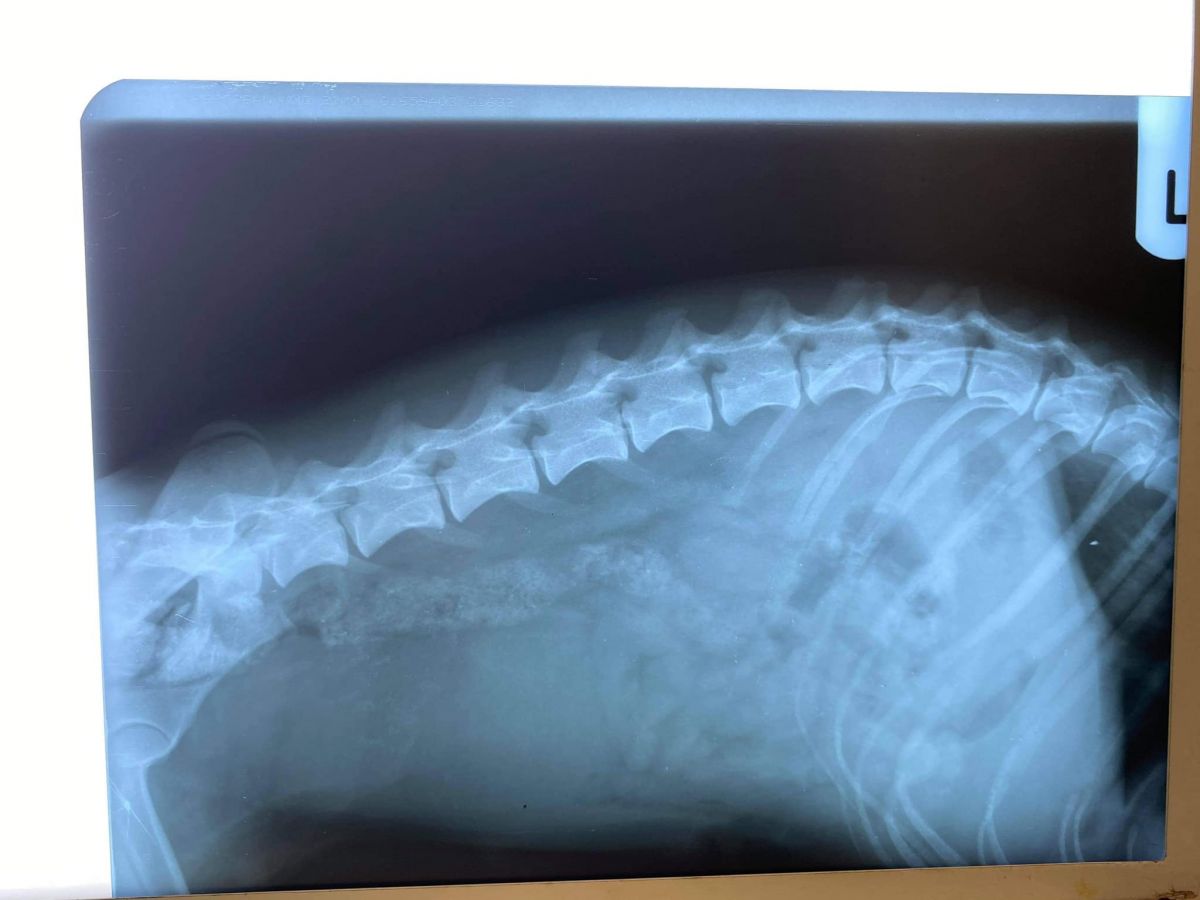

”Am reușit să o stabilizăm iar starea ei este una  bună acum, însă din păcate în urma radiografiilor prezintă o deplasare vertebrală, motiv pentru care momentan este paralizată”,

O intervenție de neuro-chirurgie de fixare a corpurilor vertebrale afectate i-ar da șansa unei vieți normale, să poată să meargă din nou.